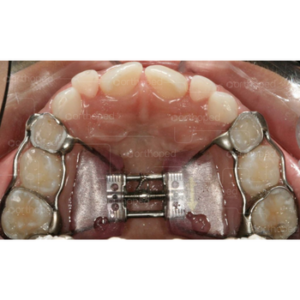

A expansão da maxila em pacientes Classe II, além de corrigir a relação transversa, possibilita a melhora, ou até mesmo a correção da Classe II através da acomodação mandibular mais anterior no período de estabilização.

O procedimento de expansão maxilar elimina as interferências oclusais permitindo que a mandíbula se desloque para anterior.

A correção espontânea da Classe II pode ocorrer em até 12 meses após o procedimento de expansão, sendo que clinicamente essa melhora pode não ser observada em todos os pacientes.

Observe no caso clínico acima a melhora na relação ântero-posterior da mandíbula somente após a expansão maxilar, mostrando que muitas vezes temos melhora no posicionamento da mandíbula após a correção da atresia maxilar transversal.